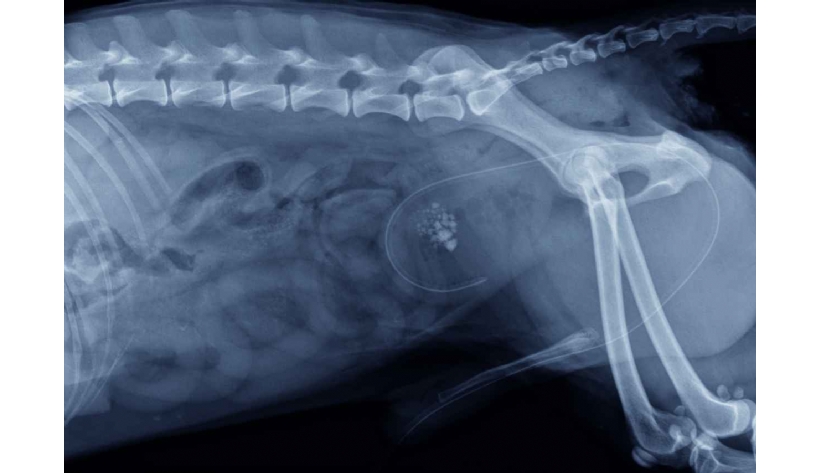

Photo n° 1 : Radiographie abdominale en vue latérale montrant des calculs urétraux et vésicaux.

Des clichés radiographiques abdominaux montrent un chapelet de calculs dans l'urètre médian et dans la vessie (photo n° 1).